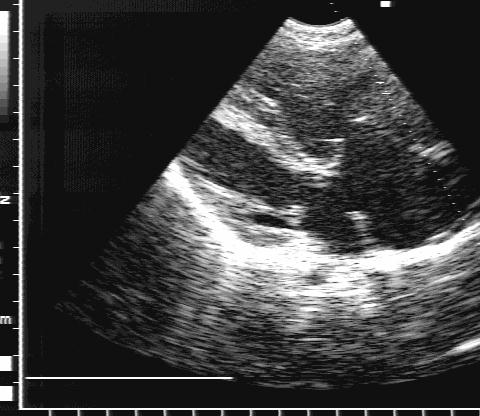

Двухмерная ЭхоКГ:

Прямая визуализация дефекта (рис.75).

1. Вторичный дефект проявляется дефицитом структуры в области овального окна.

Вторичный дефект межпредсердной перегородки.

Рис.75.

Вторичный дефект

межпредсердной

перегородки.